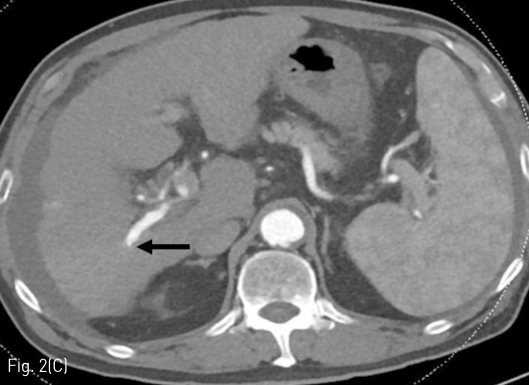

Fig 3D

(D) Additional embolization was performed with a mixture of Lipiodol and NBCA (volume ratio, 3:1).